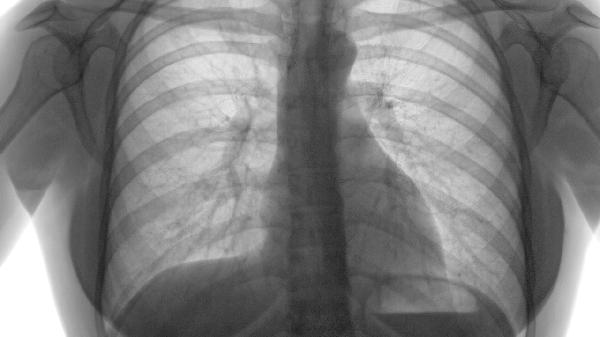

3、诊断与鉴别:哮喘的诊断主要依据症状、肺功能测试和气道高反应性测试;肺气肿的诊断则依赖于肺功能测试、影像学检查如胸部CT和血气分析。两者在肺功能测试中均表现为气流受限,但肺气肿的残气量增加更为显著。